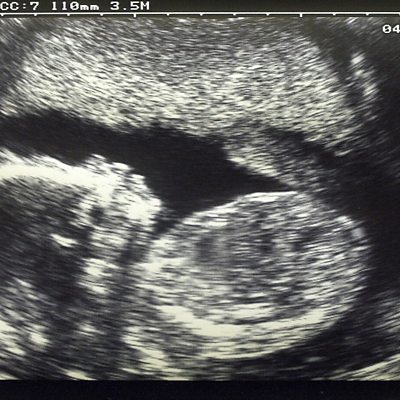

Prof Jean Twenge explains why women should treat some fertility statistics with caution.